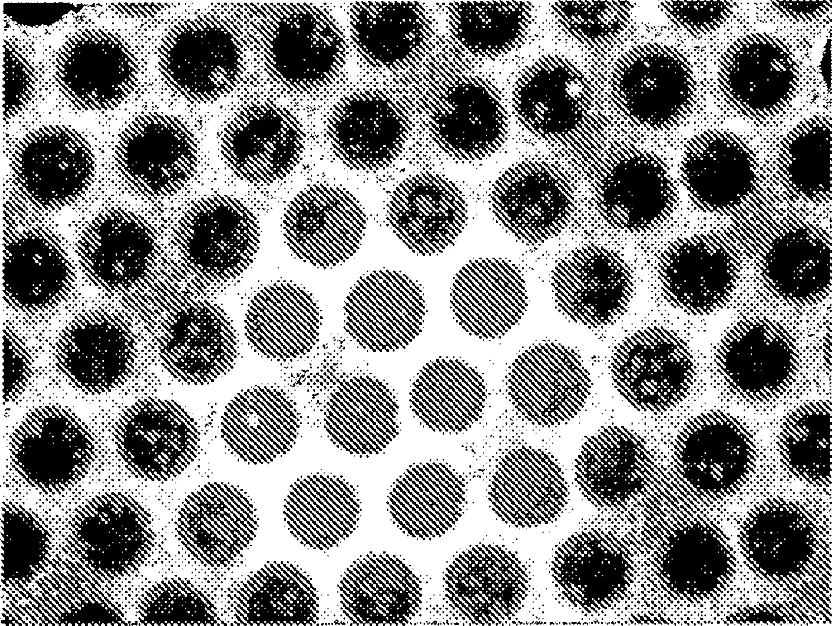

Systems, devices, and methods for specific capture and release of biological sample components